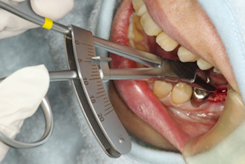

3.CFキャリパーを使い骨壁の厚さを予測する。

φ1.0mm深さ5mmまで形成されたプレ・パイロット窩にCFキャリパーの測定軸を挿入し10mmまでパイロットドリルでドリリングをおこなった場合の頬側および舌側(口蓋側)の骨壁の厚さを予測する。

頬側あるいは舌側にプレ・パイロット窩が片寄りすぎたり傾斜し過ぎている場合は位置や角度を変えてプレ・パイロット窩を形成し直す。

※ CTキャリパーは結果を実測するための診断器具であるのに対し、このCFキャリパーの最大の特徴は、パイロット窩が適切かどうかを予測できることにある。

適切でないと判明した時には試行錯誤によってプレ・パイロット窩を修正することができる。